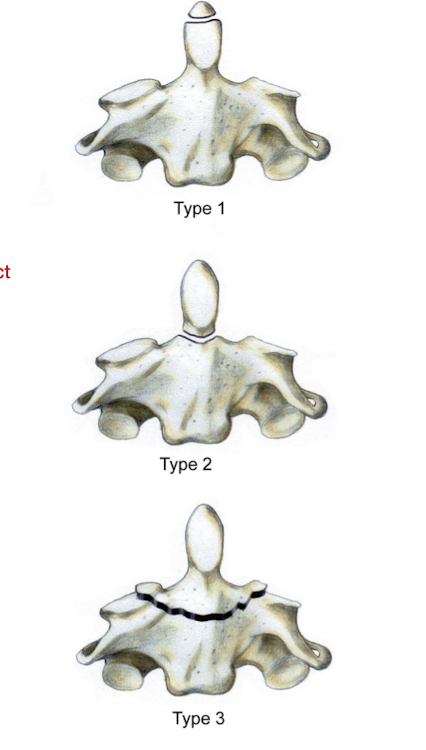

Fracture of the Axis: Dens

AKA:

__% of C/S Fx

Higher chance of __ involvement due to attachments of what 2 ligaments?

MC:

Often occurs w __ trauma

AKA:

Ondontoid Fx

20%

Neurological Involvement due to attachments of Alar and Transverse Ligs

MC C/S Fx for ≥ 65

Minimal Trauma

Fracture of the Axis: Dens

What are the 3 types of Odontoid Fractures?

Type 1:

Avulsion of the Hip

Type 2:

At junction of dens on the body of the axis

Type 3:

Below the junction of the dens

Fracture of the Axis: Dens

Which of the 3 types of Odontoid Fx is the most difficult to heal?

Why?

Type 2

Intact transverse and alar lig w poor bony contact